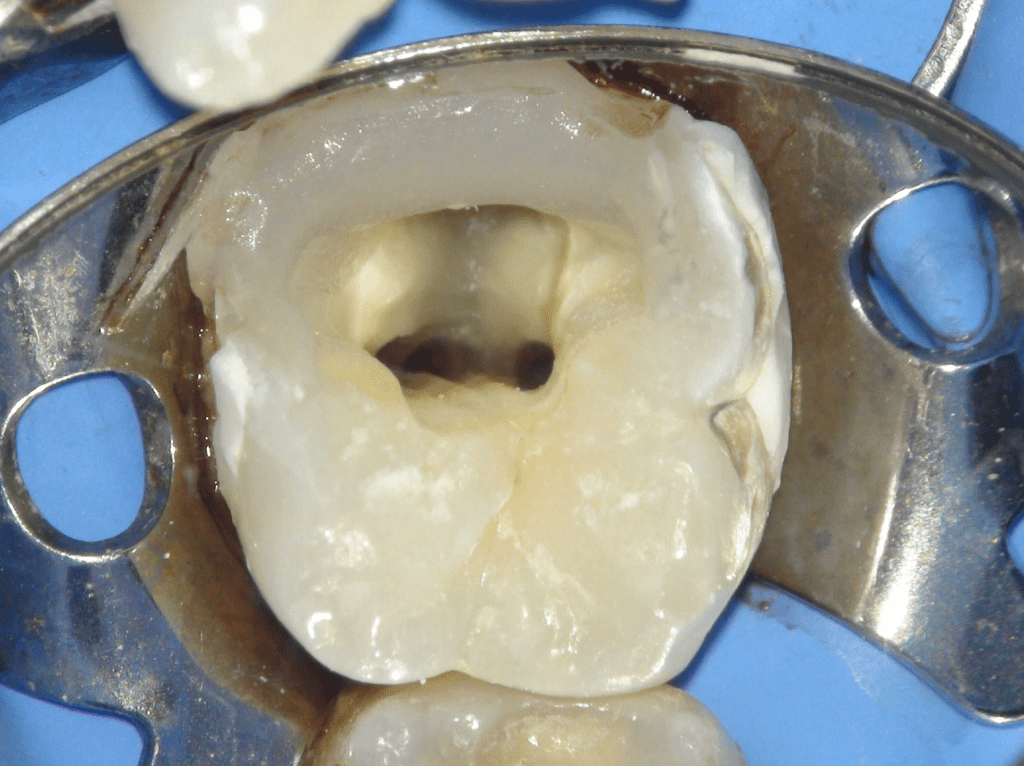

Pulpotomía biodentine + reco preendio